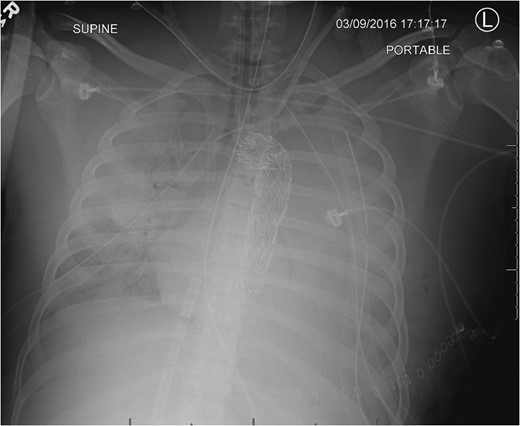

CXR following chest closure on postop day 3 demonstrated the aortic stent, multiple life support lines and bilateral lung opacification from the severe persistent respiratory failure.

He slowly improved and by postop day 11, the ECMO cannulas were discontinued. He later developed a pericardial effusion which required open drainage (postop day 18); however, the respiratory and renal failure eventually resolved. He later required surgery on his left hand fracture and subsequent debridement of the left groin. He was transferred to inpatient rehab on hospital day 35 and was discharged home by hospital day 44 without gross neurologic sequela.